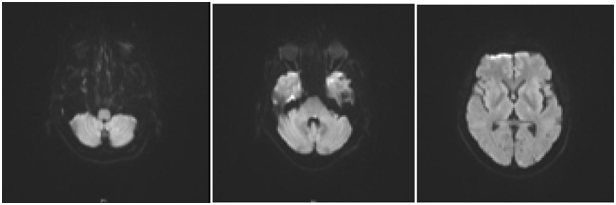

Figure 2 MRA/MRI Brain: Likely acute infarcts in the left cerebellum, occipital lobe, include the left longitudinal fasciculus which would account for the patient’s symptoms.

The CT thorax and CT pulmonary angiogram showed marked pulmonary infiltrates and thrombi. There was a thombus in the segmental right lower lobar pulmonary area, with an infracted region in the right lung base. There was also another thrombus in the anterior segmental branch of the left lower lobe pulmonary artery. Subsequently, the patient suffered from opthalmoplegia due to stroke in the ward. The MRI/MRA revealed acute infarcts in the left cerebellum, occipital lobe and left medial longitudinal fasciculus. He also developed gut vasculitis and a perforated transverse colon (Figure 3) (Figure 4). The findings on CT abdomen and pelvis were consistent with that of a small/medium vessel vasculitis. Multifocal ischemic colitis was seen involving the right lateral and posterior walls of the rectum as well as the inferior wall of the mid transverse colon with suggestion of perforation on both sides. The superior rectal artery was thrombosed as well. The patient then underwent emergency laparotomy with resection of small bowel and stoma creation. Post-operatively recovered well and was discharged two weeks after. Currently he is on follow up with rheumatologist, neuroopthalmologist and general surgeon (Figure 5).